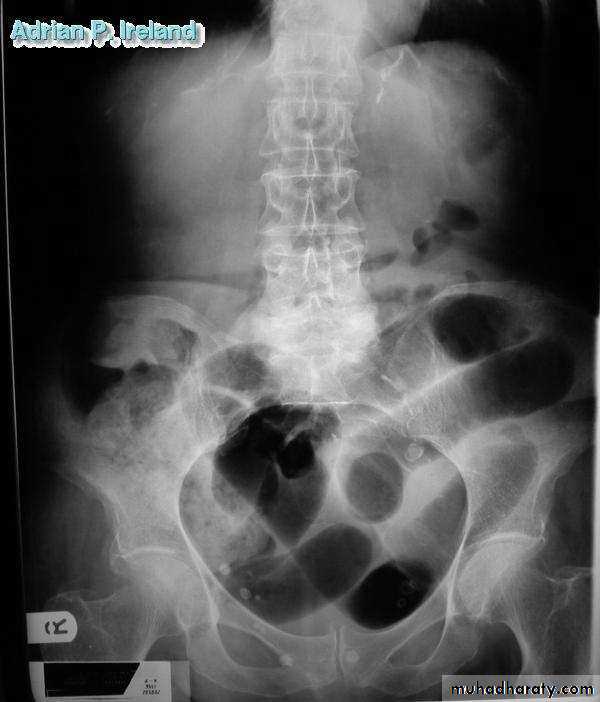

• Radiology; PFA, Large bowel obstruction

• Radiology; CT, Large bowel obstruction